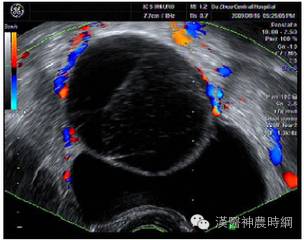

B超声象图:B超显象是目前辅助诊断子宫内膜异位症的有效方法,主要用以观察卵巢子宫内膜异位囊肿,其声象图的特征为:囊性肿块,边界清晰或不清。如囊肿周围粘连重,则边界不清;如囊肿与子宫或周围组织粘连少,则边界清晰。囊肿多为中等大小,囊肿内可见颗粒状细小回声,是囊液粘稠表现。有时因陈旧性血块浓缩机化而出现较密集的粗光点图象,呈混合性肿块状。

肿块常位于子宫后侧,可见囊肿子宫伴随症。囊肿自发破裂时,声象图示后凹陷,囊肿较前缩小。腹腔镜检查:腹腔镜检查是目前诊断子宫内膜异位症的新标准,通过腹腔镜可直接窥视盆腔,见到异位病灶即可明确诊断,且可进行临床分期,以决定治疗方案。